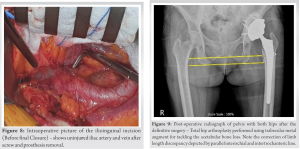

Furthermore, early prosthesis loosening, just 3-year post-primary surgery, made us suspicious of prosthetic joint infection. It had to be ruled out even in the absence of any clinical signs of infection and hence we felt a two-staged intervention to be appropriate. Intraoperative cell salvage facilities were not available to us. Attempting to remove the screw without adhesiolysis will lead to vessel avulsion injury, having very high mortality. Pre-operative total leukocyte counts (TLC), erythrocyte sedimentation rate (ESR), and C-reactive protein (CRP) levels were found to be within normal limits. In the first stage, adhesions between the vessels and the intrapelvic screw were released using an ilioinguinal incision to prevent any possible injury to the vessels while removing the screw. This stage was performed in the presence and guidance of a vascular surgeon who was well-versed in dealing with vascular complications. During the procedure, it was found that the screw was strongly adhered to the vessel. The external iliac vessels had to be carefully dissected away from the screw by releasing the adhesions all around (Fig. 6).

Once the adhesions were released, the external iliac vessels were protected with saline-soaked gauze, the incision was temporarily closed and the patient was carefully repositioned from supine to lateral decubitus position. The hip joint was exposed through the posterior approach. After removal of the femoral component and the acetabular polyethylene liner, the screws were gently removed to explant the acetabular shell. The broken screw was completely embedded in the pelvic bone and could not be removed. We decided to leave it behind as it was not abutting any important structure. Intraoperative frozen section was not available at our hospital and therefore tissue samples were collected and sent for bacterial cultures. Antibiotic-laden polymethylmethacrylate cement containing 80mg Gentamicin and 2g Vancomycin was used to fill the acetabular cavity and proximal femoral canal (Fig. 7). Incision was closed, keeping a negative suction drain. The integrity of the external iliac vessels was reconfirmed (Fig. 8) and then the anterior incision was finally closed. Postoperatively, the patient was observed closely for any signs of internal bleeding and delayed injury to vessels. Infection assessment with parameters such as TLC, ESR, CRP levels, and daily drain output was done. Intraoperative samples for bacterial cultures turned out to be inconclusive, showing no bacterial growth after 2 weeks of incubation period. Definitive surgery was then scheduled and during this surgery, the cement filler was extracted and the acetabular bone defect was reconstructed using trabecular metal augment in a flying buttress mode [5]. Impaction bone grafting using morselized allograft was done to build up the medial acetabular floor and a multi-hole uncemented acetabular shell was implanted. Acetabular screws were placed carefully according to the maximum bone available for fixation, the screw lengths were determined using the pre-operative CT scan. Screw insertion in the posterosuperior zone was not feasible due to the trabecular metal augment. A long hydroxyapatite-coated femoral stem was press-fitted. Post-operative radiograph shows correction of the limb length discrepancy (Fig. 9). In bed and bedside rehabilitation was started on the same evening. Toe-touch weight bearing, giving 20–30% of body weight was started on the third post-operative day with the help of a walker and full weight bearing was gradually allowed after 6 weeks